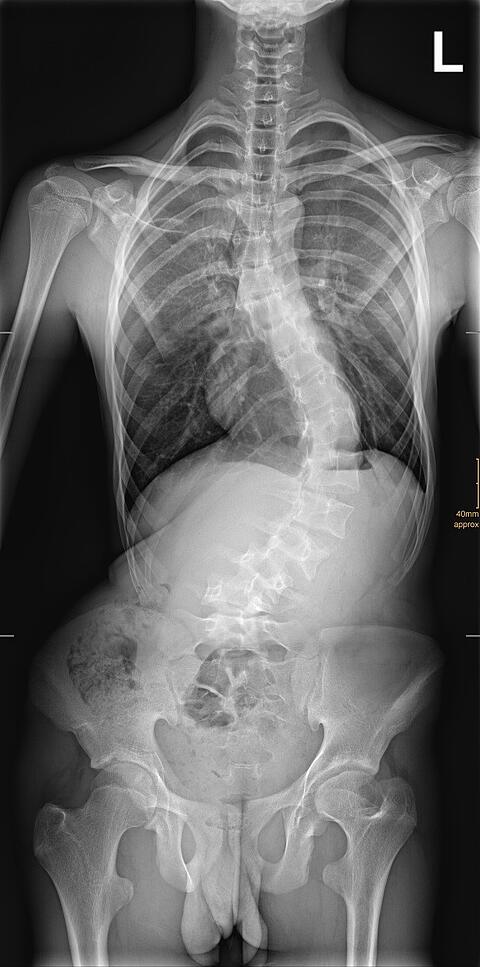

Für die Entscheidung der Behandlung und der Dokumentation des Therapieerfolges sind Röntgenaufnahmen der gesamten Wirbelsäule sehr wichtig. Da es sich bei den Patienten um Kinder und Jugendliche handelt ist eine besonders schonende Röntgendiagnostik, das heißt mit möglichst wenig Röntgenstrahlen verbunden Untersuchung, wichtig.

Neben stehend sehen sie eine solche Röntgenaufnahme der gesamten Wirbelsäule und des Beckens. Für eine solche Aufnahme müssen 4 Bilder aufgenommen werden und dann werden diese zusammengesetzt. Hierbei ist eine verzerrungsfreie Aufnahme jeder einzelnen Ebene wichtig. Bei unserem Multitom fährt die Röntgenröhre und der entsprechende Detektor parallel die Etagen ab und es kommt zu einer optimalen und verzerrungsfreien Darstellung. Gleichzeitig ist die verwendete Strahlenexposition extrem niedrig, da die neuesten Röntgentechnologien verwendet werden. In dem Beispiel erkennt man eine massive Verkrümmung der Lendenwirbelsäule nach links.